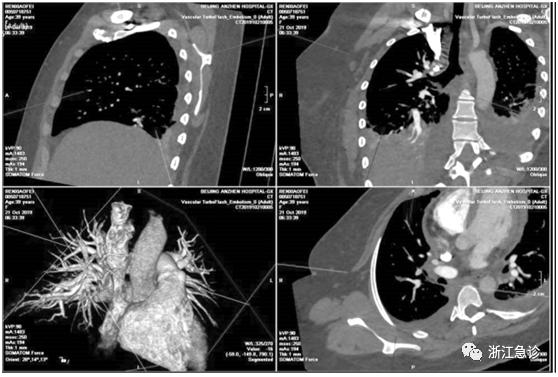

患者意识清,血压正常(110 /65mm Hg),心率快(110 次/min),双下肺呼吸音减低,心音弱,心律齐,双下肢不肿。C-反应蛋白轻度升高(36.24mg /L);血常规:白细胞计数基本正常( 白细胞计数 10.39 × 109 /L,中性粒细胞计数77.4%),轻度贫血(红细胞计数3.47 × 1012 /L,血红蛋白108 g /L,血小板计数119 × 109 /L)。血中D-二聚体明显升高(5410 ng /mL),反映心肌损伤和心衰的指标均正常(肌钙蛋白0.31 ng /mL,B-型钠尿肽30pg/mL)。在吸氧条件下血气分析显示氧分压偏低(PaO2 87.8mmHg)。超声心动图提示:少量心包积液( 左室后壁积液深6 mm,左室心尖积液深6 mm,右房顶积液深5 mm)。下肢静脉多普勒超声提示: 右侧股总静脉( 留置深静脉导管侧) 附壁血栓。心电图可见QⅢTⅢ,考虑急性肺栓塞( 见图3)。胸部CT 提示: 心包积液,密度偏高;双侧胸腔积液、双肺下叶、左肺舌叶实变、部分膨胀不全? ;左侧气胸( 见图1)。CT 肺动脉造影提示肺栓塞,累及右上肺动脉前段分支( 见图2) 。

左侧气胸(2019 年10 月21 日)

胸部CT: 肺栓塞累及右上肺动脉前段分支(2019 年10 月21 日)